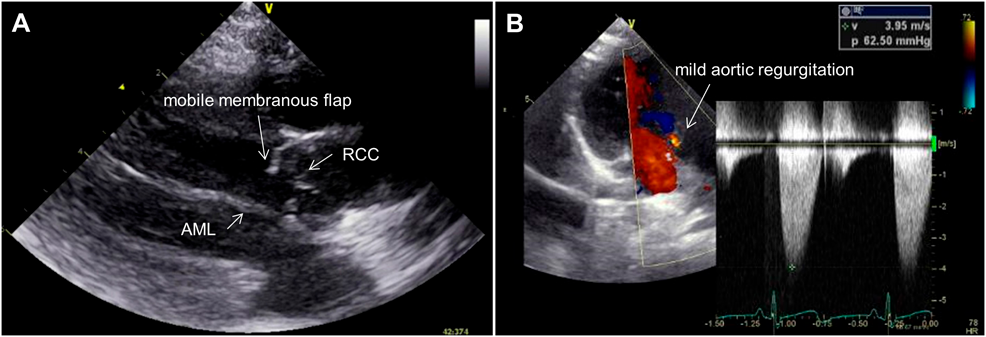

A systolic ejection heart murmur had been noted since infancy. A diagnosis of DSS was made because of a membranous structure detected by cardiac echocardiography. The flap length increased from 1.5 to 5.7 mm. The trans-DSS peak blood flow velocity increased from 1.7 to 4.0 m/s over the course of approximately 6 years, and mild aortic regurgitation developed (Fig. 1A, 1B; Supplementary Video S1). Cardiac catheterization revealed a resting peak pressure gradient of 40 mmHg between the left ventricle (LV) and ascending aorta (AAo), mild aortic regurgitation, and a persistent left superior caval vein. We considered the progression of DSS and newly developed aortic regurgitation as indications for surgical repair.

Fig. 1 Preoperative echocardiographic findings (A) A long-axis view of the flap under the aortic valve. (B) A three-chamber view of the left ventricle outflow tract

AML, anterior mitral leaflet; RCC, right coronary cusp.